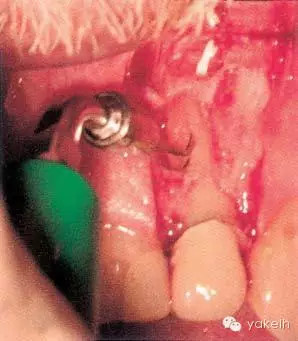

¤¤在征得患者同意后,最終選擇根管外科手術(shù)修復(fù)穿孔。局麻下翻開三角形全厚黏骨膜瓣,充分暴露骨和根面;使用刮匙去除穿孔上覆蓋的肉芽組織,暴露穿孔和樁(圖5.4.2a);使用外科專用渦輪手機(jī)配以金剛砂小球鉆,去除樁的尖端;使用超聲銼去除根管末端的牙膠,并進(jìn)行根管預(yù)備(圖5.4.2b);預(yù)備后的根管與穿孔部位使用IRM嚴(yán)密封閉(圖5.4.2c);瓣復(fù)位、縫合固定,拍攝術(shù)后X線片(圖5.4.3a);3天后拆線。

圖5.4.2(a)去除肉芽組織,暴露穿孔和樁。